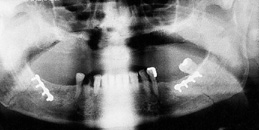

Osteosynthesis procedures are performed at our clinic according to modern international standards. Mini and micro plates made of titanium and special medical steel are used to stabilize the fractured bones. Especially for the treatment of temporomandibular joint fractures a joint plate was developed in our clinic. The development and application of resorbable osteosynthesis materials is at the same time a research task of the clinic.